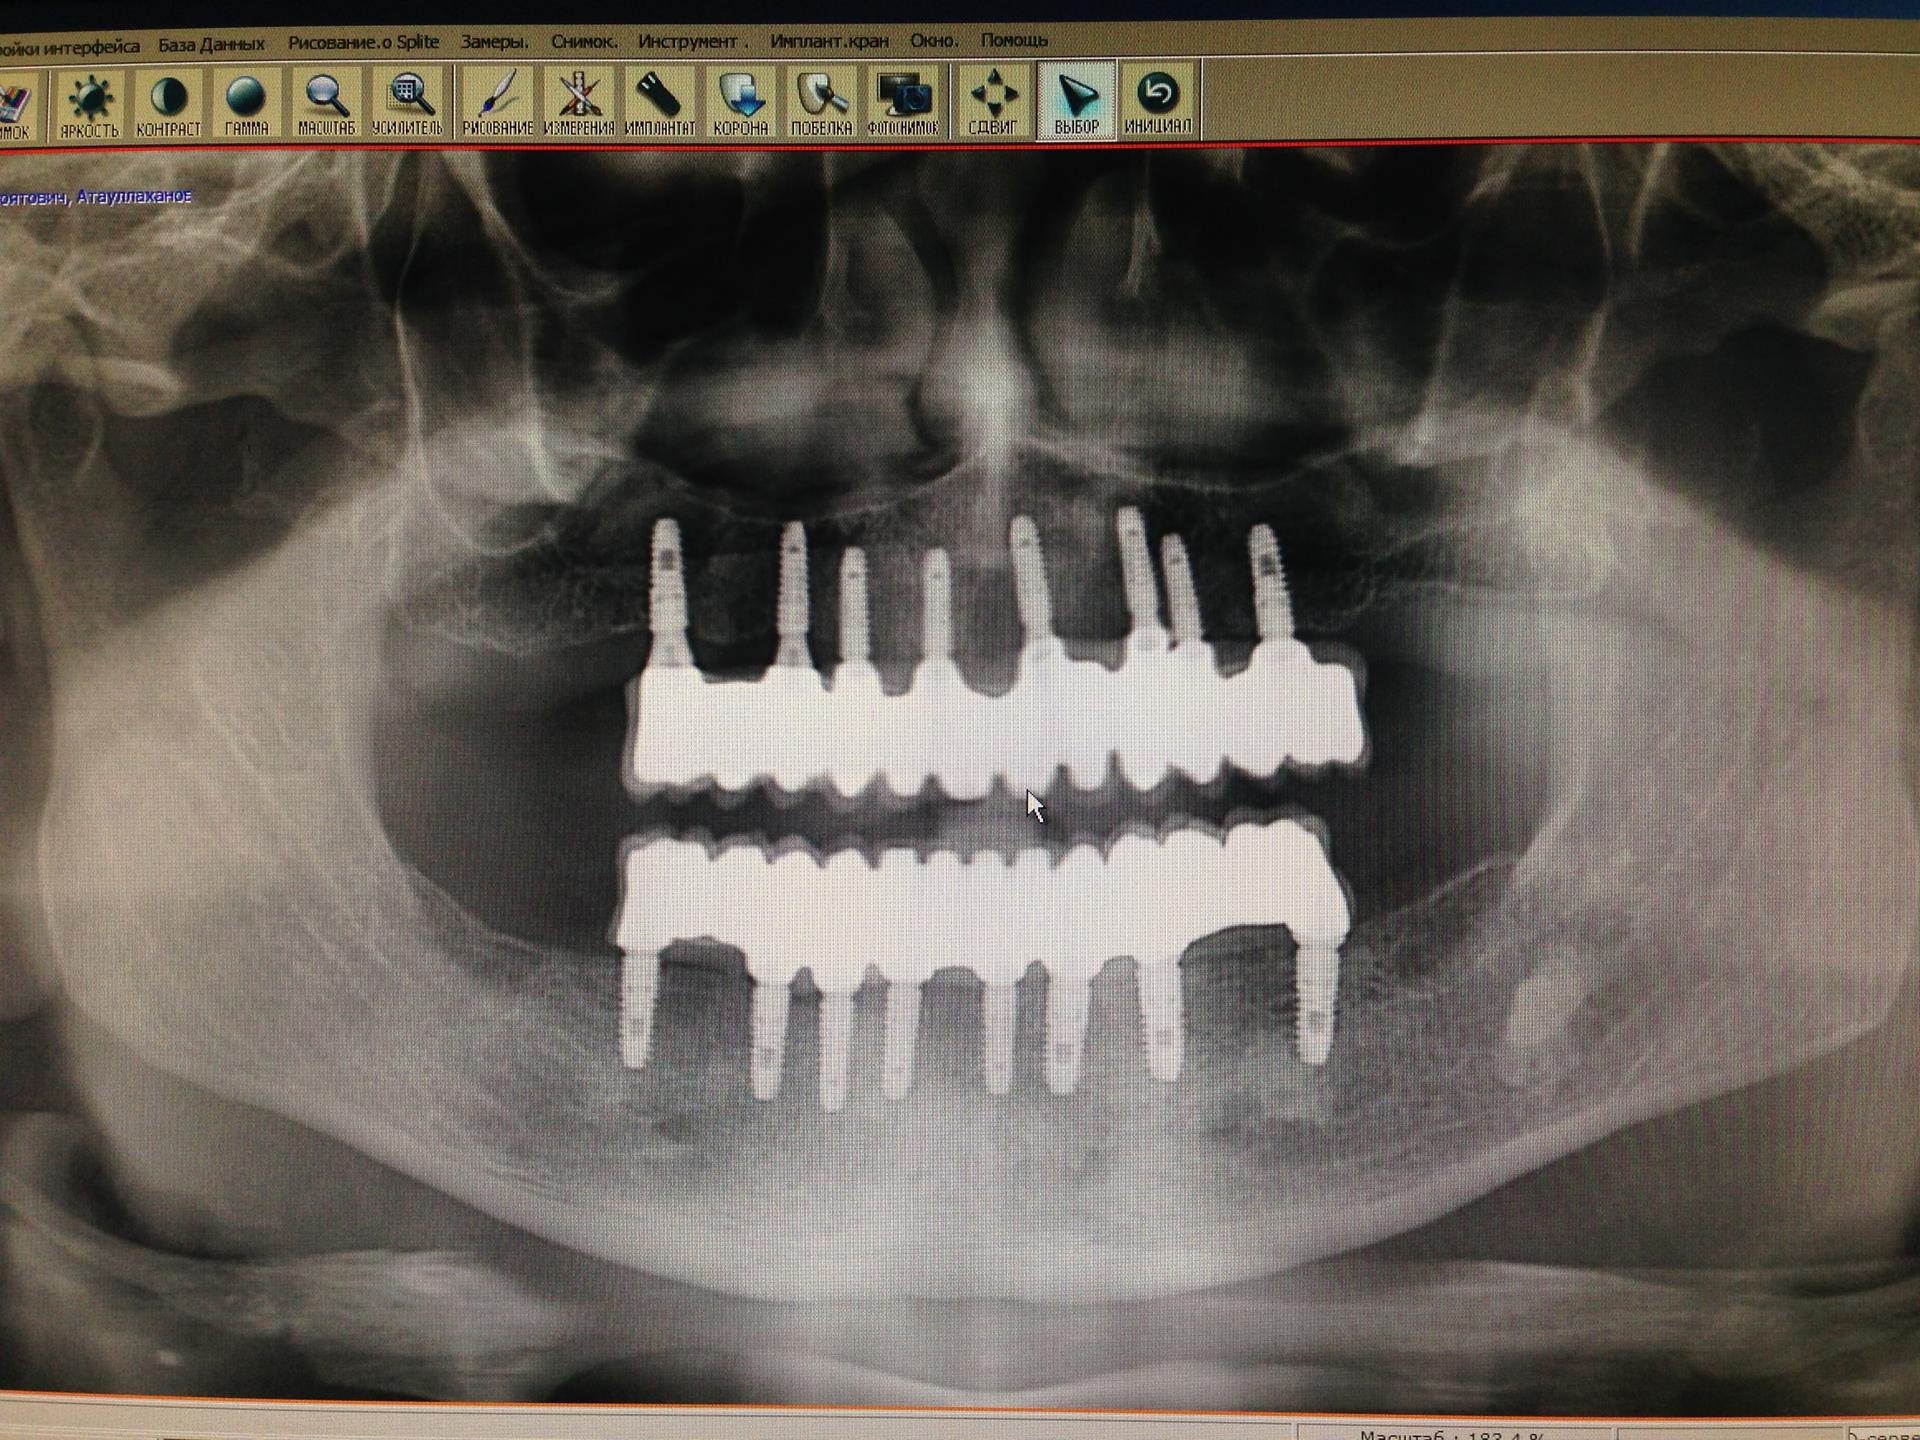

Исследование на рентгене после имплантации зубов

Раздел: Снимки-откровения